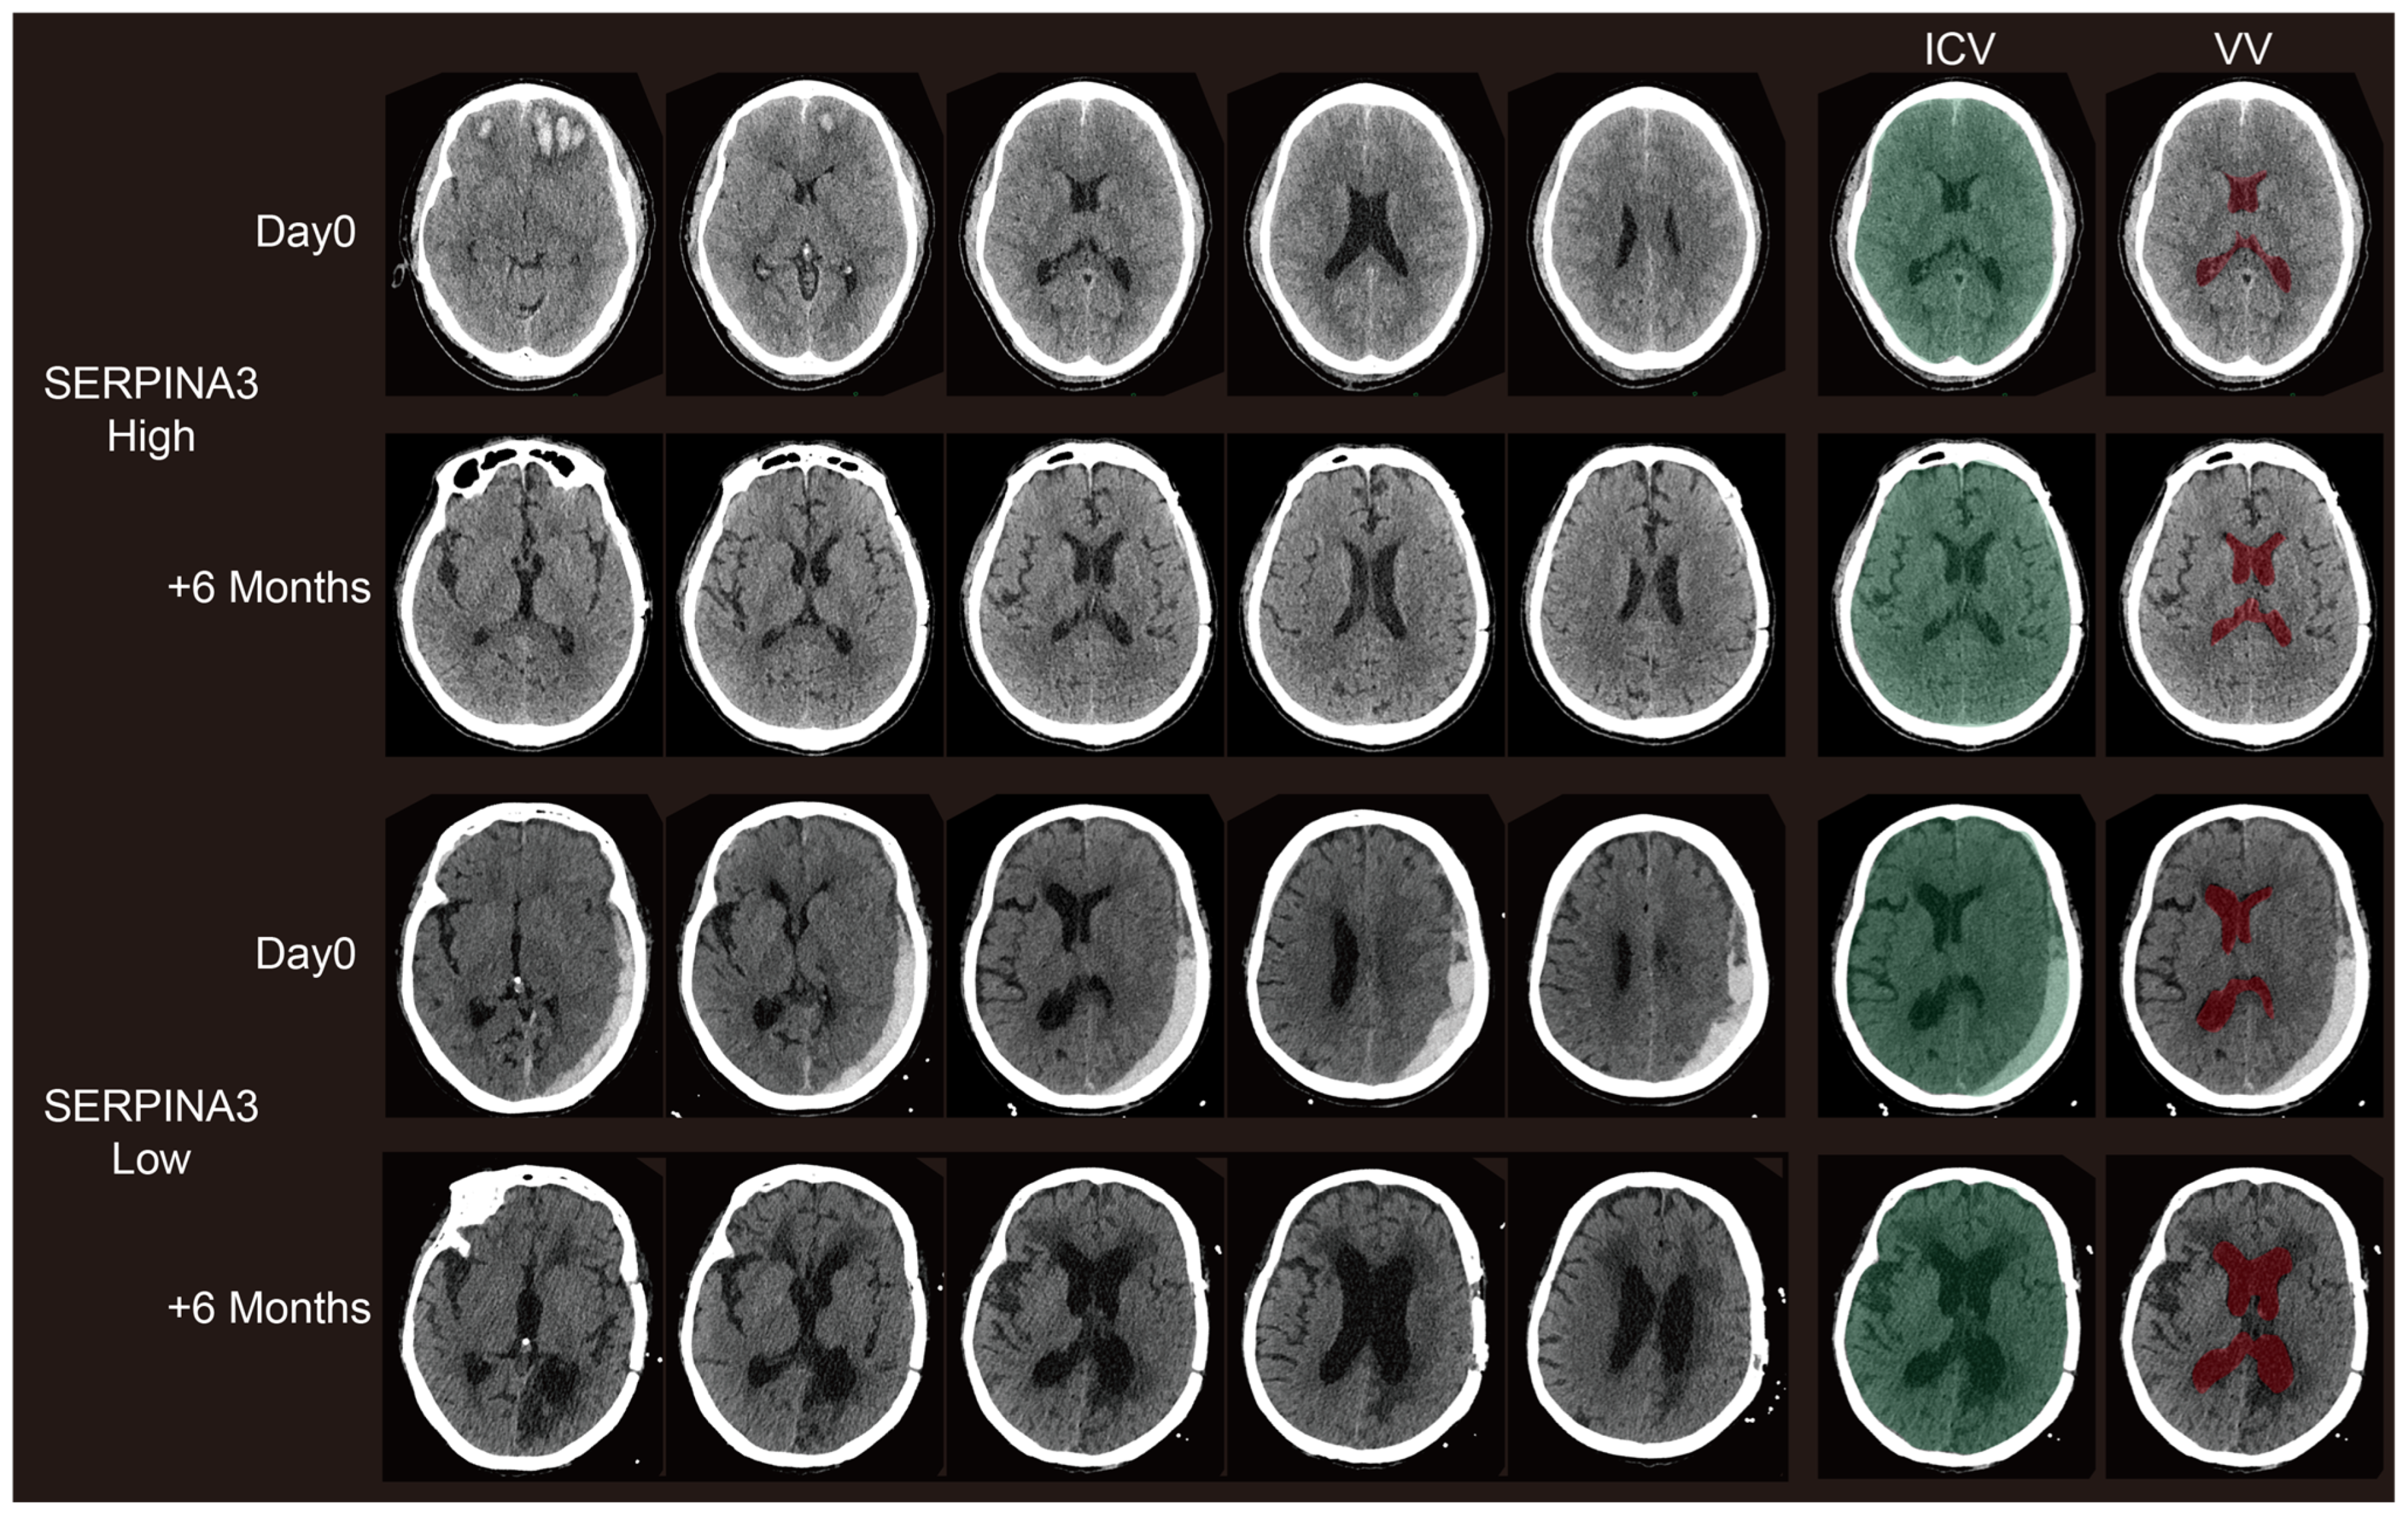

3.4. Long-Term Structural Changes on CT Images Correlate with Preoperative Serum SERPINA3 Levels

Concerning the VBRs, upon stratifying patients based on their SERPINA3 levels and examining the VBR across groups with high and low serum SERPINA3 concentrations, a notable difference emerged: a significantly lower VBR was observed in the high-SERPINA3 group compared with the low SERPINA3 group at 6 months post-trauma (p < 0.05), as illustrated in Figure 3b. However, the difference in VBRs measured based on CT scans obtained preoperatively was not significant (Figure 3a and Figure 4). Furthermore, our analysis revealed a negative correlation between the VBR and SERPINA3 concentration at 6 months post-trauma (p < 0.01), as depicted in Figure 3c and Figure 4.

Figure 4. Representative paired CT scans of patients in high-SERPINA3 group (the first and second lines) and-low SERPINA3 group (the third and fourth lines) at day 0 (the first and third lines) and 6 months postoperatively (the second and fourth lines). The ICV column stands for the selection of the intracranial volume (ICV). The VV column stands for the selection of the ventricle column (VV). The selection of both the ICV and VV were controlled via visual inspection.